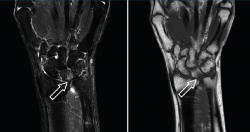

Dentro de las pruebas de imagen a realizar, son obligatorias la proyección posteroanterior (PA) de muñeca en posición neutra y una proyección PA en pronación y con el puño cerrado para poder evaluar una posible varianza positiva dinámica. Las radiografías pueden mostrar una esclerosis o quistes subcondrales en la cabeza del cúbito, el extremo proximal cubital del semilunar o el extremo proximal radial del piramidal(9). En casos severos, pueden observarse osteofitos a nivel de la articulación cubitocarpiana. De nuevo, es importante evaluar la presencia de signos artrósicos al nivel de la ARCD y la morfología de la articulación en el plano coronal, puesto que pueden condicionar la elección de la mejor opción quirúrgica. En la radiografía lateral se debe evaluar si existe subluxación de la ARCD con prominencia dorsal de la cabeza del cúbito. Es de gran ayuda y muy recomendable realizar radiografías de ambas muñecas para comparar las imágenes con la muñeca contralateral. Estrictamente hablando, no sería siempre necesario solicitar otras pruebas de imagen como la resonancia magnética (RM) para poder diagnosticar este síndrome, pero es cierto que esta puede dar detalles minuciosos sobre cuáles son las estructuras lesionadas y, además, es útil para detectar otras posibles patologías ocultas(9). En las fases iniciales, el cartílago articular afectado puede presentar signos de fibrilación y condromalacia. También se puede detectar hiperemia o edema en las zonas afectadas (Figura 3), esclerosis subcondral o cambios quísticos. La RM –y, más específicamente, la artro-RM– es especialmente útil para valorar la integridad del CFCT, del ligamento LT y para valorar otras posibles causas de dolor cubital de la muñeca cuando hay dudas sobre el diagnóstico.

Figura 3. Imagen de resonancia magnética que muestra edema en el hueso semilunar secundario a impactación cubital.